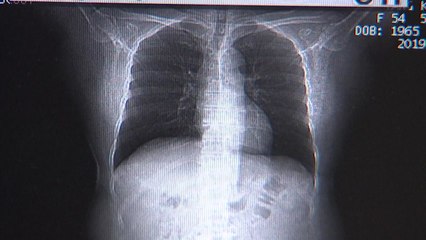

보건 당국이 성인 23만여 명을 대상으로 진행한 지역사회 건강 조사에서 담배제품 사용자는 22.6로 나타났습니다. br br 지난해보다 0.4p, 소폭 증가한 수치입니다. br br 코로나19 유행 당시 주춤했던 흡연율이 계속 증가한 건데, 남성 흡연자는 줄고 여성 흡연자는 늘었습니다. br br 지역별로 담배제품 사용률이 가장 높은 곳은 강원이었고, 최저 수준을 보인 곳은 세종이었습니다. br br 주목할 만한 점은 일반담배와 전자담배 흡연율인데, 일반담배 흡연율은 꾸준한 감소세를 유지한 반면, br br 액상형, 궐련형 전자담배 사용률은 지난해보다 0.6p 늘어난 8.7를 기록하는 등 증가세가 뚜렷했습니다. br br 정부는 소비자 경각심을 높이기 위해 담뱃갑에 흡연 위험성을 부각하는 강한 경고 문구와 그림을 넣기로 했습니다. br br 궐련형 담뱃갑 경고 그림은 모두 10종류로, '수명 단축'이나 '기형아 출산' 등은 빠지고 안질환과 말초혈관 질환 등 세부 질환이 새롭게 추가됐습니다. br br 또, 경고 문구는 '폐암'과 같은 단어형 표현에서 '폐암으로 가는 길' 등 보다 직관적인 문장형 표기로 바뀝니다. br br YTN 백종규입니다. br br 영상편집ㅣ이은경 br 디자인ㅣ백승민 br 자막뉴스ㅣ이 선, 이도형 br br #YTN자막뉴스 br br br br ※ '당신의 제보가 뉴스가 됩니다' br [카카오톡] YTN 검색해 채널 추가 br [전화] 02-398-8585 br [메일] social@ytn.co.krbr br ▶ 기사 원문 : ▶ 제보 안내 : , 모바일앱, social@ytn.co.